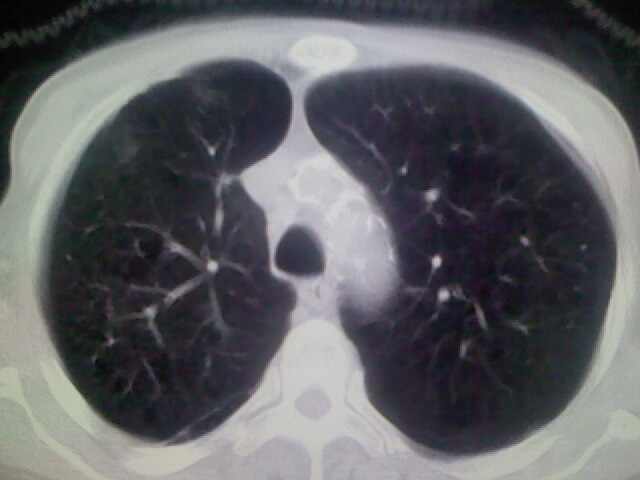

男,70y,胃占位,重度贫血,黑便3月余,伴恶心,纳差,乏力

肺内考虑原发(周围型肺癌)

右上肺周围型肺癌,肝内多发低密度影---转移瘤?建议增强;胃壁明显增厚.

1)考虑右肺上叶周围型肺癌并纵隔及右颈部淋巴结转移,肝脏多发性转移。2)肺气肿。3)冠状动脉及主动脉钙化。

支持右肺上叶周围型肺癌伴肝内多发转移.胃建议充盈后重扫描.慢性支气管炎伴肺气肿.